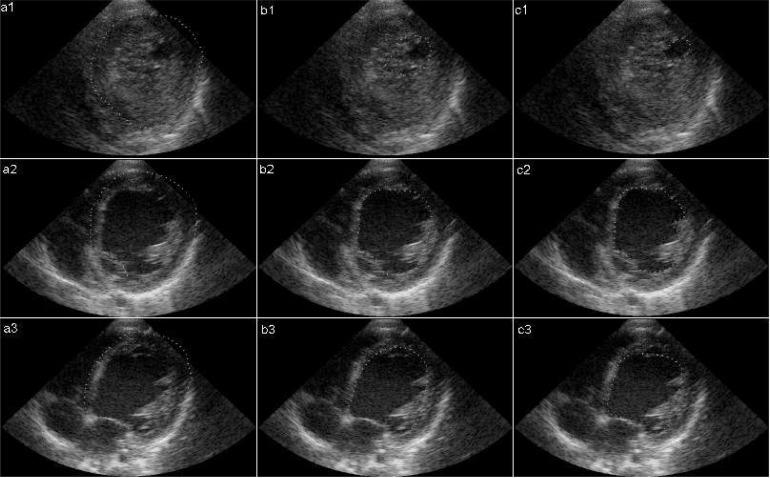

Although there are several echocardiographic criteria, there is not yet a general consensus about the diagnosis of left ventricular noncompaction. The current criteria are mostly based on the areas with maximal noncompaction in the heart. The echocardiographer may miss this maximal point leading to a misdiagnosis. Accordingly, we suggested a new method to measure the percentage of myocardial noncompaction using two-dimensional echocardiography.

In this study, the new method was examined on 4 noncompaction and 26 dilated cardiomyopathies, and 25 normal subjects. The percentage of noncompaction was measured at 3 levels (apical, papillary muscle and mitral valve) and averaged.

The mean percentages of myocardial noncompaction were 3.59±2.27, 8.86±5.52 and 34.7±26.1 in the control, dilated cardiomyopathy and noncompaction groups, respectively. A value of 17% or greater could distinguish left ventricular noncompaction from dilated cardiomyopathy with 92% specificity and 100% sensitivity and from normal subjects with 100% specificity and sensitivity. This percentage had a statistically significant association with noncompacted to compacted myocardial thickness ratio (P<0.001).